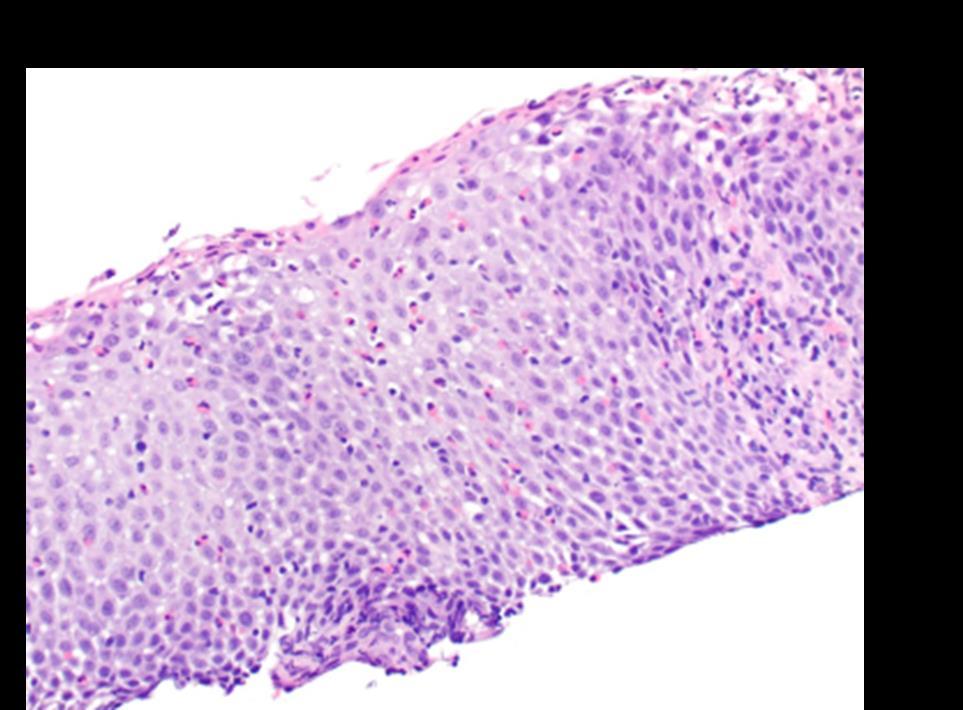

Dupilumab Improves Histologic Manifestations of Eosinophilic Esophagitis in a Real World Cohort of Pediatric Patients

Presenting Authors: Jing Marrero, MD, MPH, Emanuela Pinci, BS

Jing Marrero, MD, MPH, Emanuela Pinci, BS, Jeffrey S. Hyams, MD, Michael Brimacombe, PhD, Fabiola Balarezo, MD